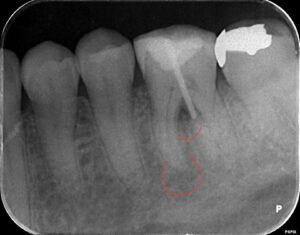

レントゲン

近心根と分岐部に病変があります。